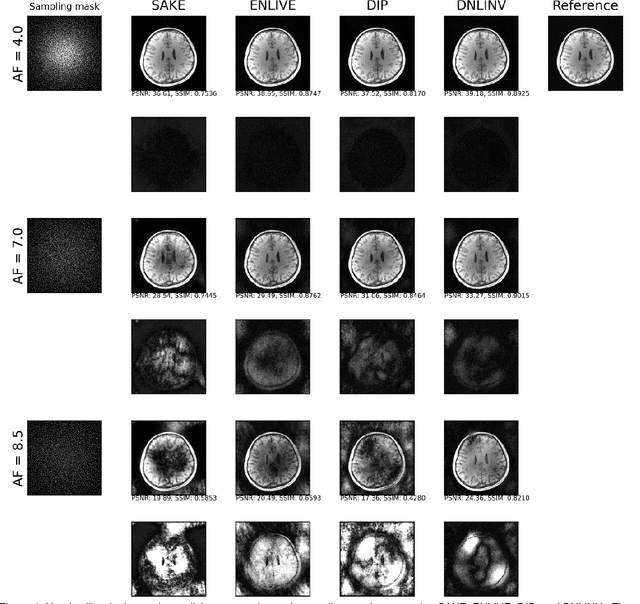

Abstract:Magnetic resonance imaging is subject to slow acquisition times due to the inherent limitations in data sampling. Recently, supervised deep learning has emerged as a promising technique for reconstructing sub-sampled MRI. However, supervised deep learning requires a large dataset of fully-sampled data. Although unsupervised or self-supervised deep learning methods have emerged to address the limitations of supervised deep learning approaches, they still require a database of images. In contrast, scan-specific deep learning methods learn and reconstruct using only the sub-sampled data from a single scan. Current scan-specific approaches require a fully-sampled auto calibration scan region in k-space that cost additional scan time. Here, we introduce Scan-Specific Self-Supervised Bayesian Deep Non-Linear Inversion (DNLINV) that does not require an auto calibration scan region. DNLINV utilizes a deep image prior-type generative modeling approach and relies on approximate Bayesian inference to regularize the deep convolutional neural network. We demonstrate our approach on several anatomies, contrasts, and sampling patterns and show improved performance over existing approaches in scan-specific calibrationless parallel imaging and compressed sensing.